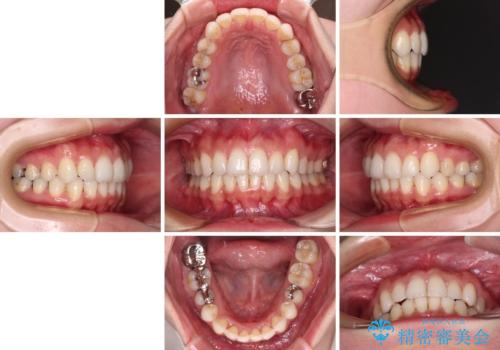

- 上下の前歯のデコボコを治したいとのことで来院された患者様です。

上下顎ともにIPR(歯と歯の間を削る)と歯列全体の拡大によって叢生が解消するように設計し、インビザラインにより治療を行うこととしました。

1日22時間の装着時間を守ってくださったので、比較的早く治療を終える予定でしたが、各国での入国制限が厳しくなり、帰国のタイミングに合わせてのんびりと治療を進めることとなってしまい、やや長期間の治療となりました。